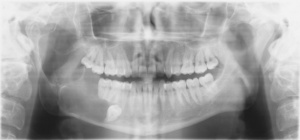

In einer extern angefertigten Panoramaschichtaufnahme bestand eine im Bereich apikal der Zähne 44-47 liegende und bis unterhalb des Processus condylaris reichende, ausgedehnte, mehrkammerige, scharf begrenzte Aufhellung. In direkter Lagebeziehung mit dem zystischen Prozess stellte sich apikal des Zahnes 46 der retinierte und verlagerte Zahn 45 dar.

Anamnestisch handelte es sich bei dieser Röntgenaufnahme um die erste Panoramaschichtaufnahme, die jemals bei dem Patienten angefertigt wurde (Abbildung 1).